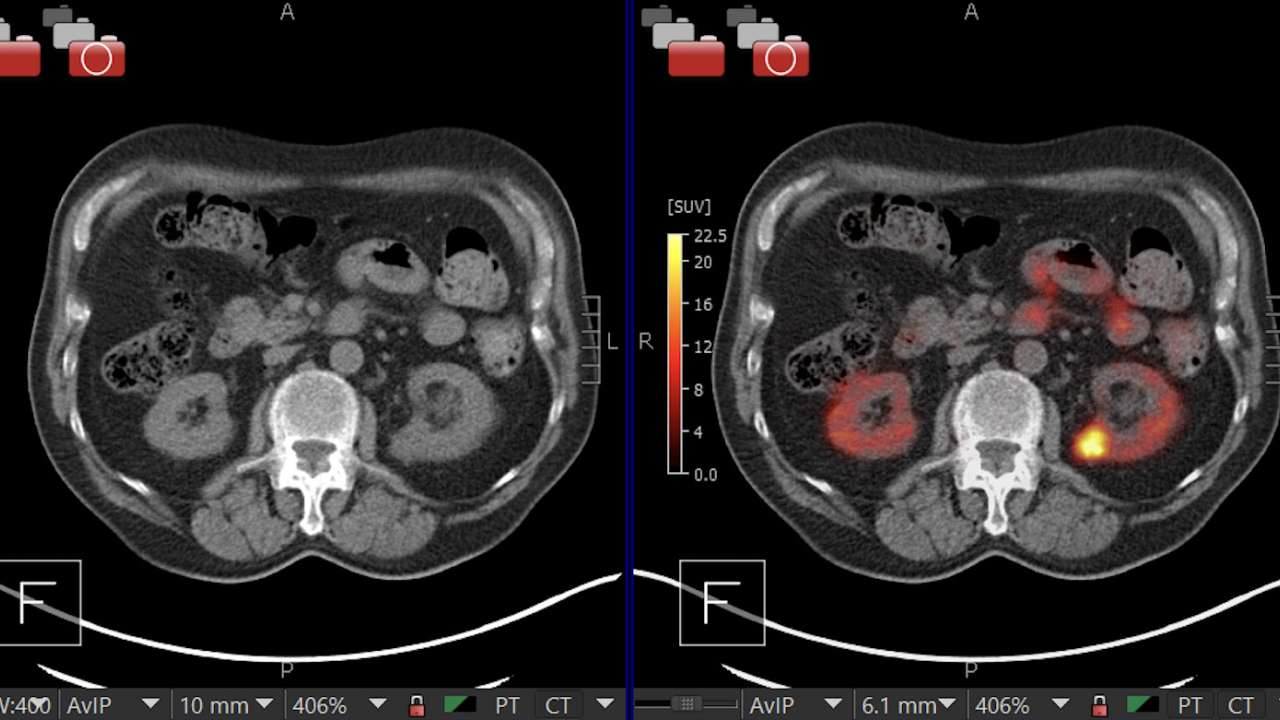

A kidney showing positive [89Zr]Zr-girentuximab PET and histologically confirmed clear-cell renal cell carcinoma. Image courtesy of Dr. Brian Shuch.

A few days after the injection, patients received a PET-CT scan to detect the radioactive part of the drug, which lights up on the scan wherever the protein is present, allowing doctors to see the cancer more clearly. By looking at the scan, doctors can determine if the kidney mass is likely to be cancerous based on whether or not the 89Zr-TLX250 has attached to the cancer cells.